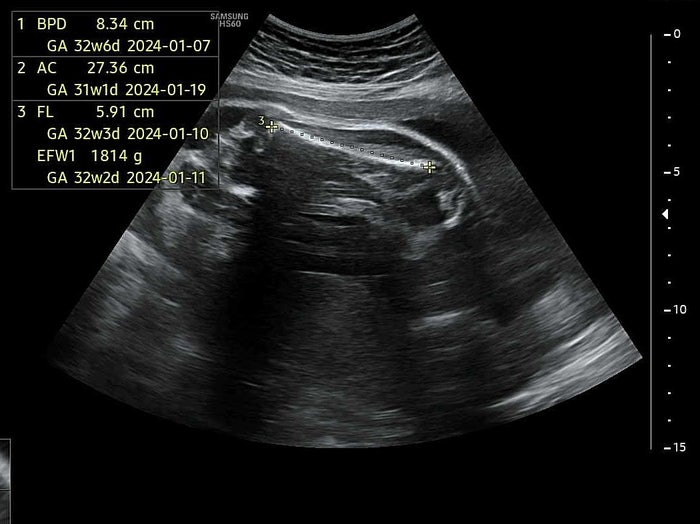

임신31주, 밑으로 내려온 아기 / 자궁경부길이 4.5cm

밑으로 내려온 아기 / 자궁경부길이 4.5cm 임산부일기 / 임신8개월 / 임신31주 임신31주 증상 -Y존통증(치...